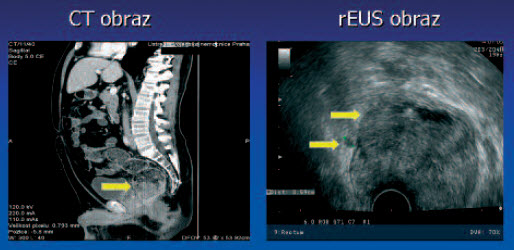

Tumor T3 N0

Tumor T3 N0 po radioterapii - kolonoskopie